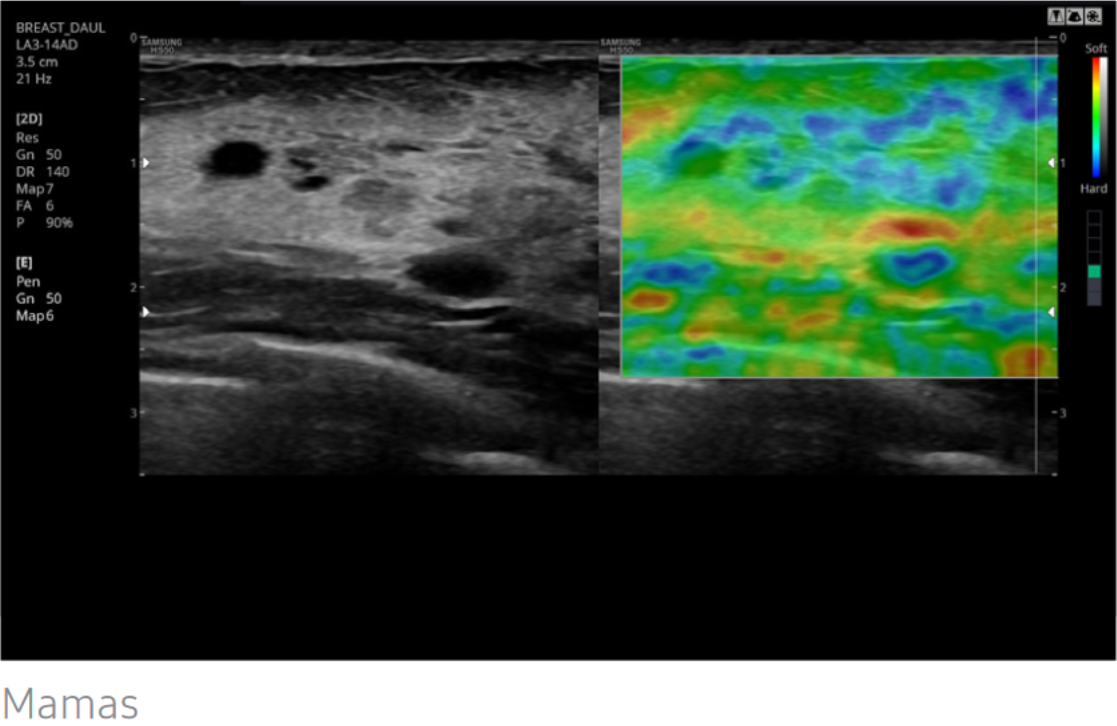

ElastoScan™

ElastoScan™, una técnica de ultrasonido de diagnóstico para la elasticidad de imagen, detecta la presencia de masas sólidas en tejidos y convierte cualquier rigidez en imágenes a color.